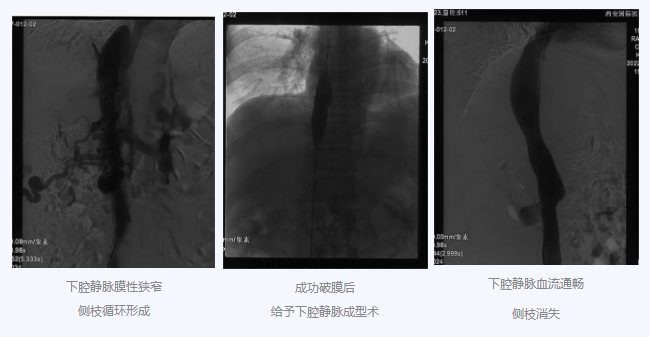

入院后,在韓國宏院長的安排下,臨床經(jīng)驗豐富的醫(yī)師給老謝做了B超、CT 等檢查,結(jié)果顯示:三支肝靜脈近心端閉塞,肝內(nèi)側(cè)枝循環(huán)形成,下腔靜脈近心房入口處隔膜樣狹窄,隨后的DSA血管造影也證實:下腔靜脈狹窄,且有側(cè)枝形成,最終確診困擾老謝20年的疾病為混合型布加綜合征,是一種罕見病。

明確診斷后,韓院長帶領團隊縝密分析老謝的病情,為其制定最佳的治療方案,考慮到老謝的根本病因是下腔靜脈阻塞,介入手術成為首選治療方法,通過微創(chuàng)介入手術,可準確打通患者的閉塞血管,癥狀迅速緩解。做好充分術前準備后,為患者行“下腔靜脈成型術”,精準定位快速貫通,閉塞的下腔靜脈順利開通,手術圓滿完成。